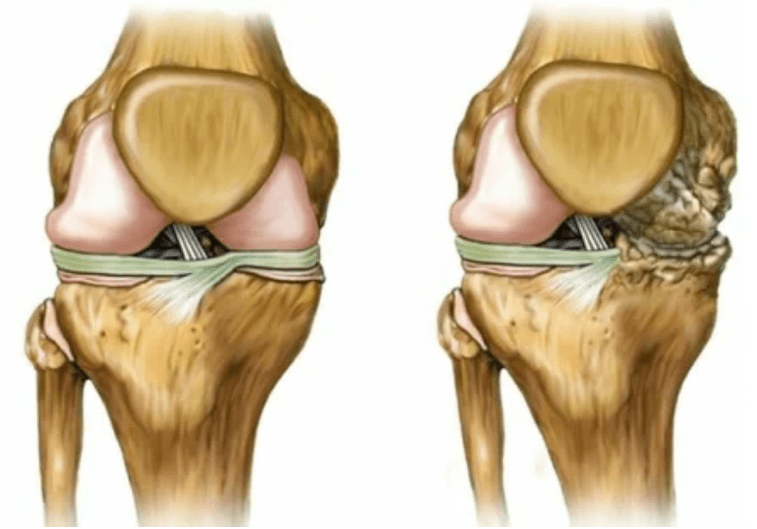

- 3 Grad. Oft gibt es Schmerzen, es ist schwierig, das Glied aufgrund von Veränderungen im Gelenk zu bewegen. Die Läsionen sind umfangreich und werden für den nackten Look spürbar. Die Verformung der Gelenkstelle tritt auf, der betroffene Bereich schwillt an und wird rot. Die Gliedmaßenachse ist gestört, was zur Komplexität der Bewegung führt. Pathologische Veränderungen produzieren die Bänder. Subluishes und Kontrakturen erscheinen. Die angrenzenden Muskeln werden verkürzt oder gestreckt, aus denen die kontraktile Funktion geschwächt wird.

Gliedmaßenverformungen. Erscheint in einer vernachlässigten Form der Krankheit, weist die vollständige Zerstörung von Knorpelgewebe und das Auftreten von Osteophyten an. In diesem Zustand steigt der Druck auf die Gelenke oben und unterhalb, aus denen die Krümmung das gesamte Glied beeinflussen kann.

Um eine Diagnose zu stellen, untersuchen Rheumatologen die Beschwerden des Patienten und verschreiben eine X -Ray -Untersuchung. Meistens wird die Radiographie in 2 Projektionen verwendet. Der Arzt untersucht das Vorhandensein dystrophischer Störungen bei hyalinen Knorpel- und Knochenfugen. Wenn die Gelenkspalt verringert ist, sind die Knochen deformiert oder abgeflacht, es gibt zystische Formationen auf der Oberfläche des Knorpels, Osteophyten sind offensichtliche Anzeichen von Arthrose. Während der Inspektion zeigt die Arthrose die Instabilität des Gelenks an: Die Achse der Gliedmaßen und Subluxation wird gestört.